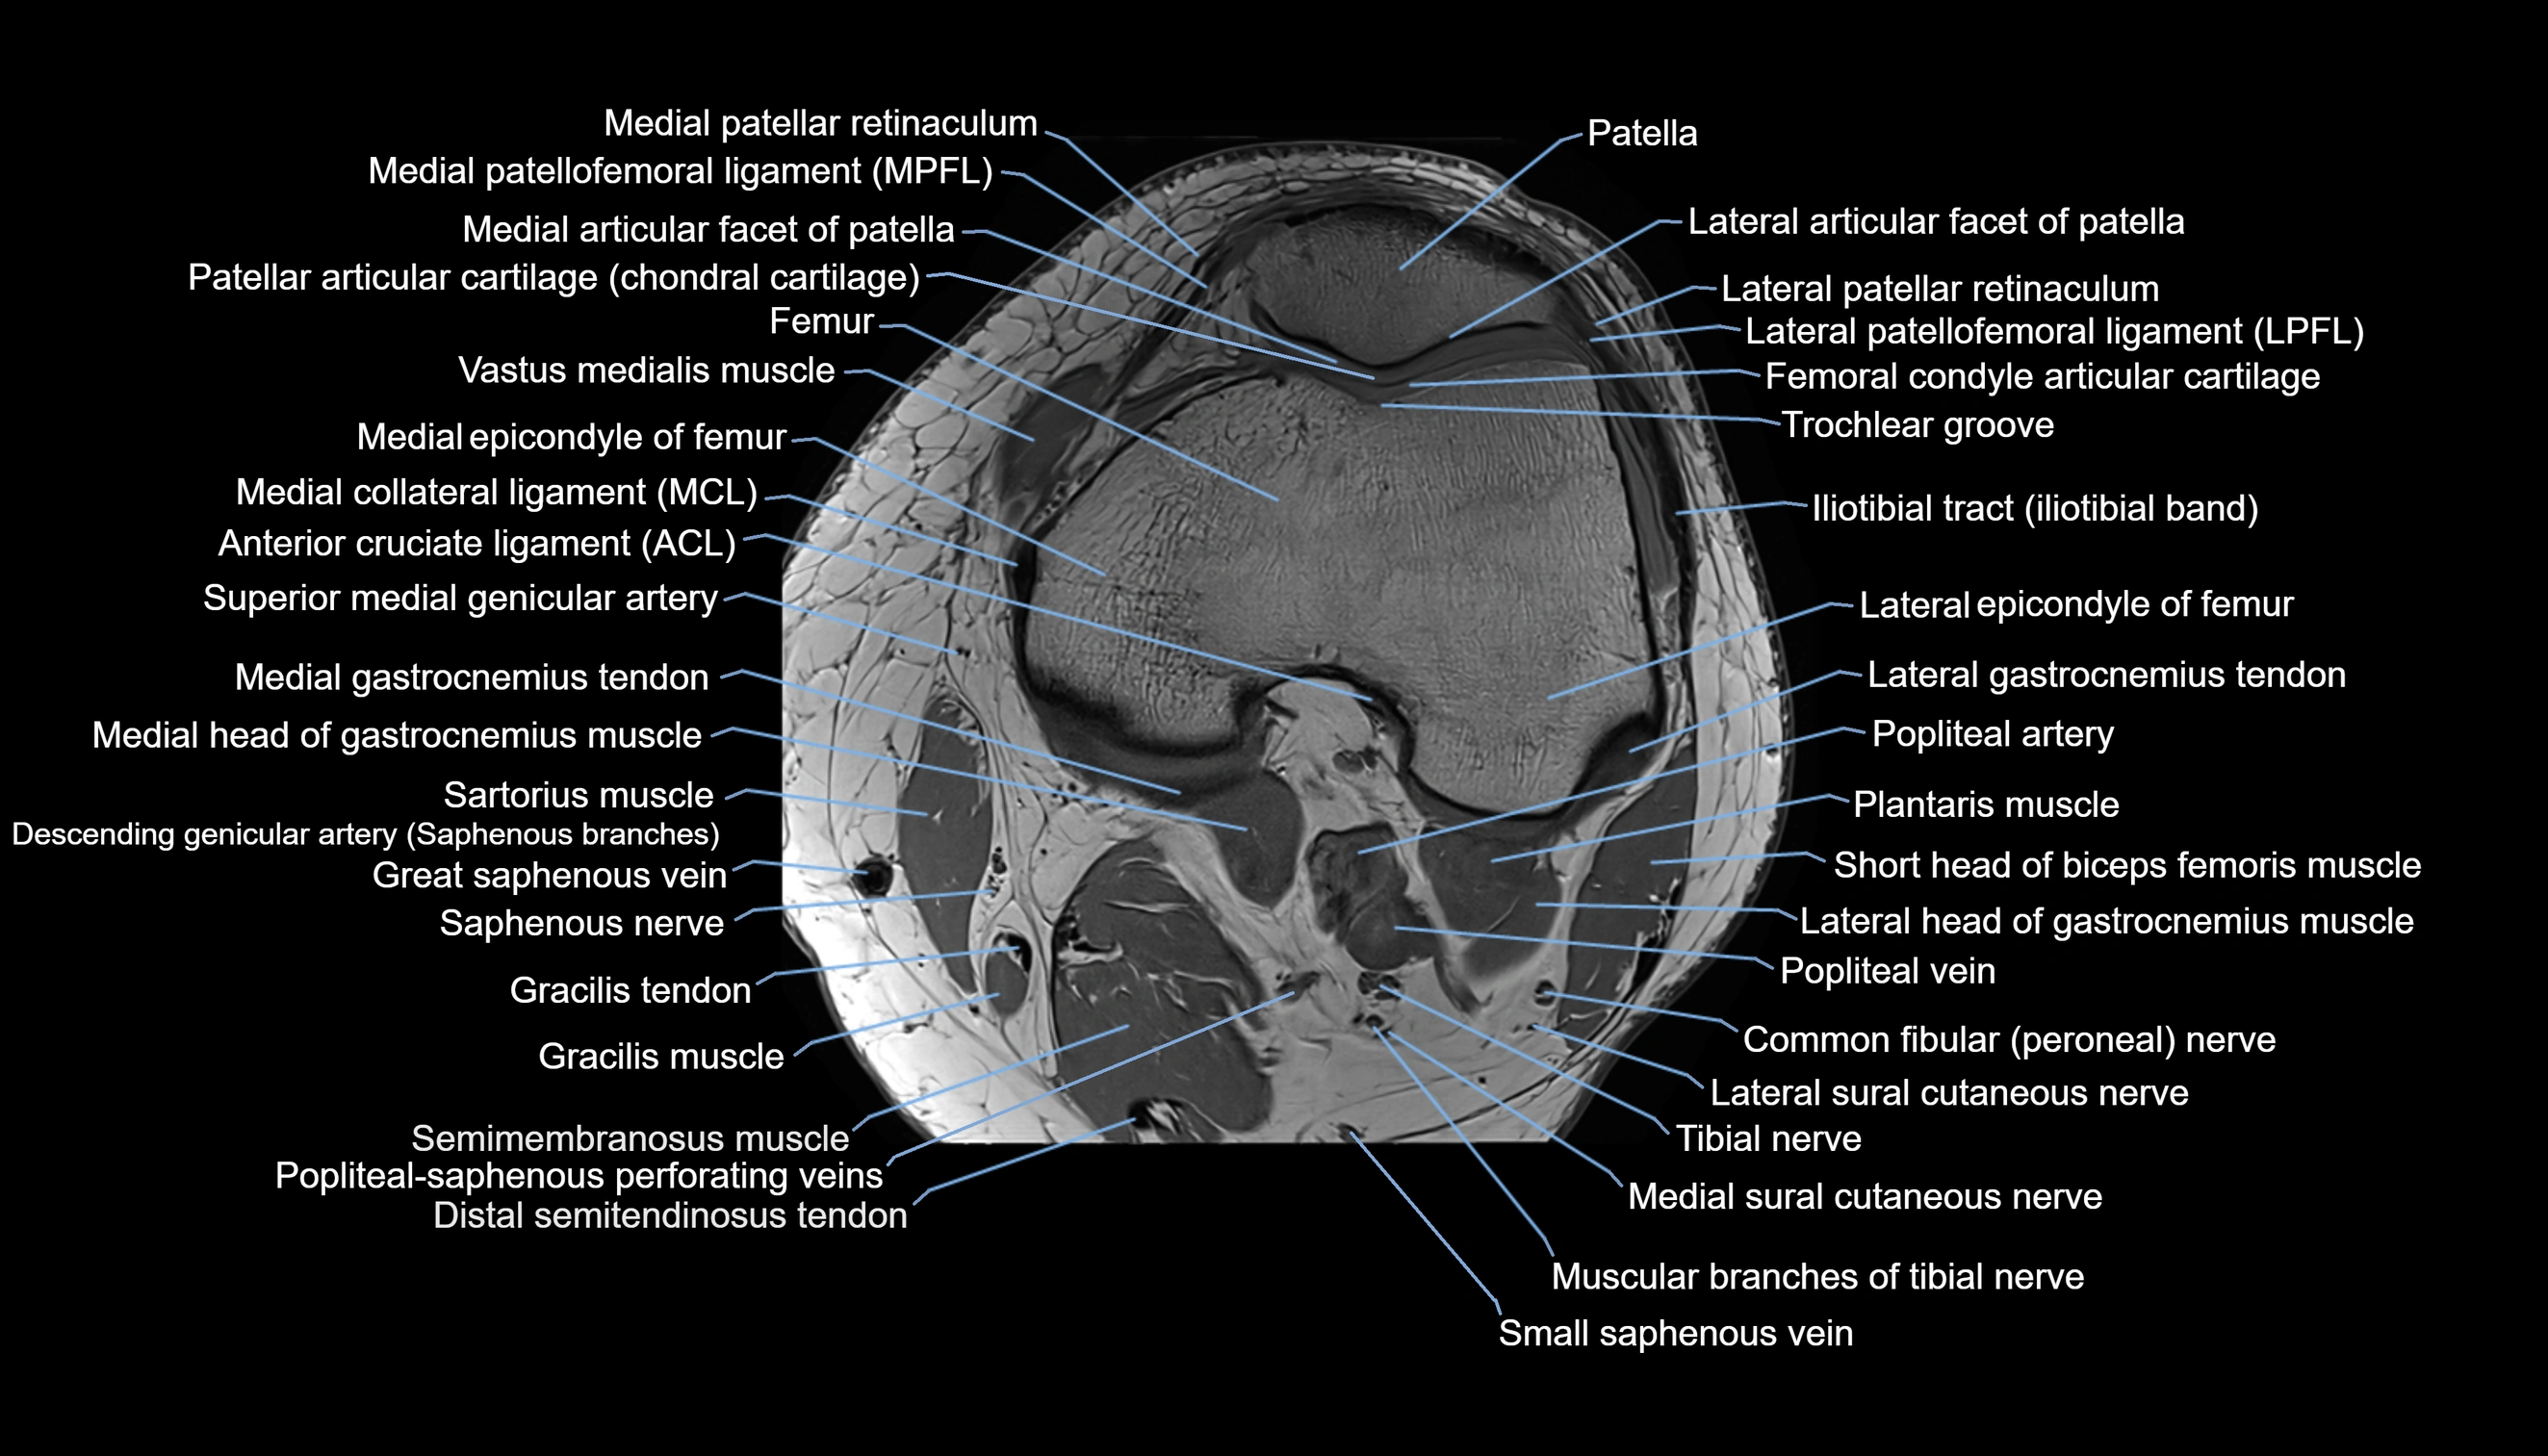

- Lateral articular facet of patella

- Lateral border of patella

- Lateral patellar retinaculum

- Lateral patellofemoral ligament

- Medial articular facet of patella

- Medial collateral ligament

- Medial condyle of femur

- Medial epicondyle of femur

- Medial gastrocnemius tendon

- Medial head of gastrocnemius muscle

- Medial patellar retinaculum

- Medial patellofemoral ligament

- Medial sural cutaneous nerve

- Muscular branches of tibial nerve

- Patella

- Patellar articular cartilage

- Popliteal artery

- Popliteal vein

- Sartorius muscle

- Semimembranosus muscle

- Small saphenous vein

- Superior medial genicular artery

- Tibial nerve

- Trochlear groove

- Vastus medialis muscle

- great saphenous vein